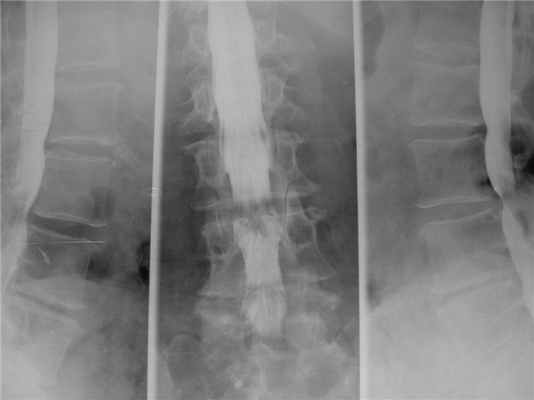

Применение жестких фиксирующих систем при спондилодезах «выключают» один или несколько позвоночно-двигательных сегментов из кинематической цепи позвоночного столба. Смежные сегменты испытывают значительную механическую перегрузку, что приводит к преждевременной деградации дисков и суставов смежного уровня, разрастанию соединительной ткани, компенсаторной гипертрофии дугоотростчатых суставов, приводящих к развитию сегментарного стеноза. Рецидивная грыжа диска и неустраненный стеноз позвоночного канала требуют повторного хирургического вмешательства.

![]()

Синдром смежного уровня. Стеноз позвоночного канала выше уровня стабилизации. Миелография.

МРТ поясничного отдела позвоночника. Синдром смежного уровня. Нестабильность позвоночного сегмента выше уровня стабилизации.